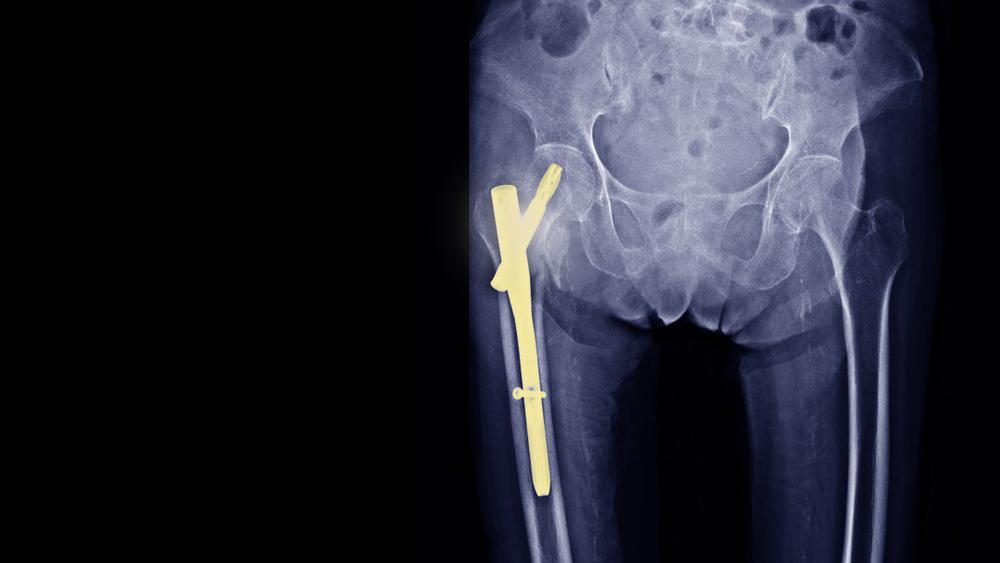

Pen adalah alat pendukung seperti pelat, sekrup, batang, dan kabel yang terbuat dari stainless steel atau titanium. Alat ini biasanya akan dokter gunakan pada operasi tulang, seperti:

Pada saat itu, dokter akan mengangkat pen melalui sayatan yang sama ketika dokter bedah pertama kali memasukkan pen ke dalam tubuh Anda.

Biasanya, dokter akan lebih kesulitan menemukan pen jenis sekrup kecil atau kawat. Oleh sebab itu, dokter akan membuat sayatan lebih besar dan menggunakan bantuan kamera X-ray.

Selain itu, dokter mungkin juga akan kesulitan untuk menemukan pen yang tertutup oleh jaringan parut atau tulang meski pen memiliki ukuran yang lebih besar.